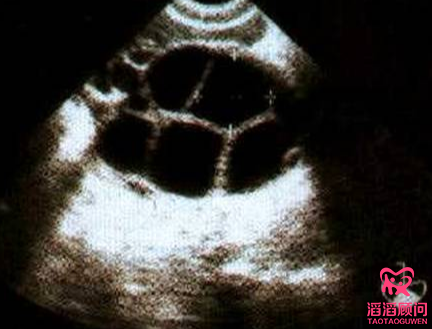

促排用药期间,医生会通过血液检查和B超来监测卵泡的发育情况,如果需要,医生会调整用药方案。若对促排环节了解比较清楚的,在整个促排过程中都能轻松舒适。

取卵手术是在注射“夜针”后的第3天早上,是一种微创手术。操作方法:在超声波引导下,医生将一根针刺入每个卵巢中吸取卵泡,这是一项非常精细的工作,每一毫米都至关重要,有经验的医生才能做取卵手术。